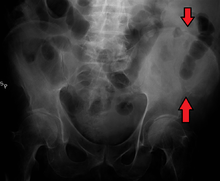

The crest of the ilium (or iliac crest) is the superior border of the wing of ilium and the superolateral margin of the greater pelvis.

The iliac crest stretches posteriorly from the anterior superior iliac spine (ASIS) to the posterior superior iliac spine (PSIS). Behind the ASIS, it divides into an outer and inner lip separated by the intermediate zone. The outer lip bulges laterally into the iliac tubercle. [1] Palpable in its entire length, the crest is convex superiorly but is sinuously curved, being concave inward in front, concave outward behind. [2]

It is thinner at the center than at the extremities.

The top of the iliac crests also marks the level of the fourth lumbar vertebral body (L4), above or below which lumbar puncture may be performed.